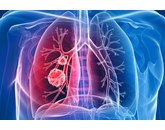

Điều trị ung thư phổi 05/08/2023 Ung thư phổi được điều trị dựa trên loại và giai đoạn ung thư, cũng như tình trạng sức khỏe chung của bệnh nhân và...

Dịch tễ học ung thư phổi 05/08/2023 Ung thư phổi đã trở thành đại dịch từ những năm 1930. Các yếu tố rủi ro được xác định bao gồm:

Chẩn đoán ung thư phổi 05/08/2023 Ung thư phổi thường không biểu hiện triệu chứng cho đến khi nó ở giai đoạn cuối, điều đó có nghĩa là kết quả điều...

Triệu chứng ung thư phổi 05/08/2023 Ung thư phổi thường không có bất kỳ triệu chứng nào trong giai đoạn đầu của bệnh, có nghĩa là rất khó phát hiện và...

Nguyên nhân ung thư phổi 05/08/2023 Nguyên nhân chính của ung thư phổi là hút thuốc, mặc dù những người không hút thuốc cũng có thể phát triển tình trạng này...